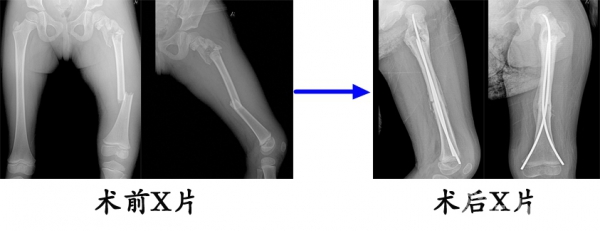

13.严某某,女,4岁,高处坠落伤(股骨颈、股骨干骨折),术后恢复颈干角、前倾角。